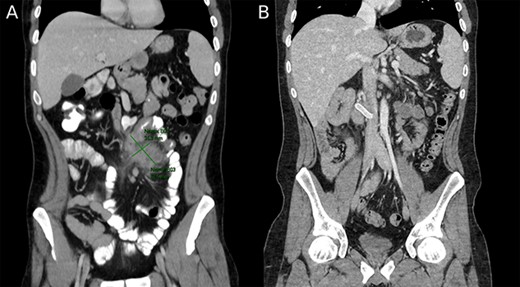

Magnetic resonance imaging (MRI) enterography conducted a year prior to the current admission demonstrated the entire colon was found to the left of the abdominal midline (Fig. 1). MRI demonstrated ileal loops in the central abdomen, a thickened bowel wall with dilated sections ~5 cm in diameter. These findings were consistent with malrotation of the bowel and small bowel obstruction.

MRI enterography depicting intestinal malrotation and ileal loops in the central abdomen dilated up to 5 cm, consistent with malrotation and a small bowel obstruction.